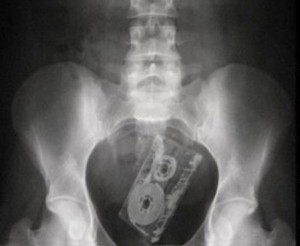

აუდიოკასეტა

6 (1)